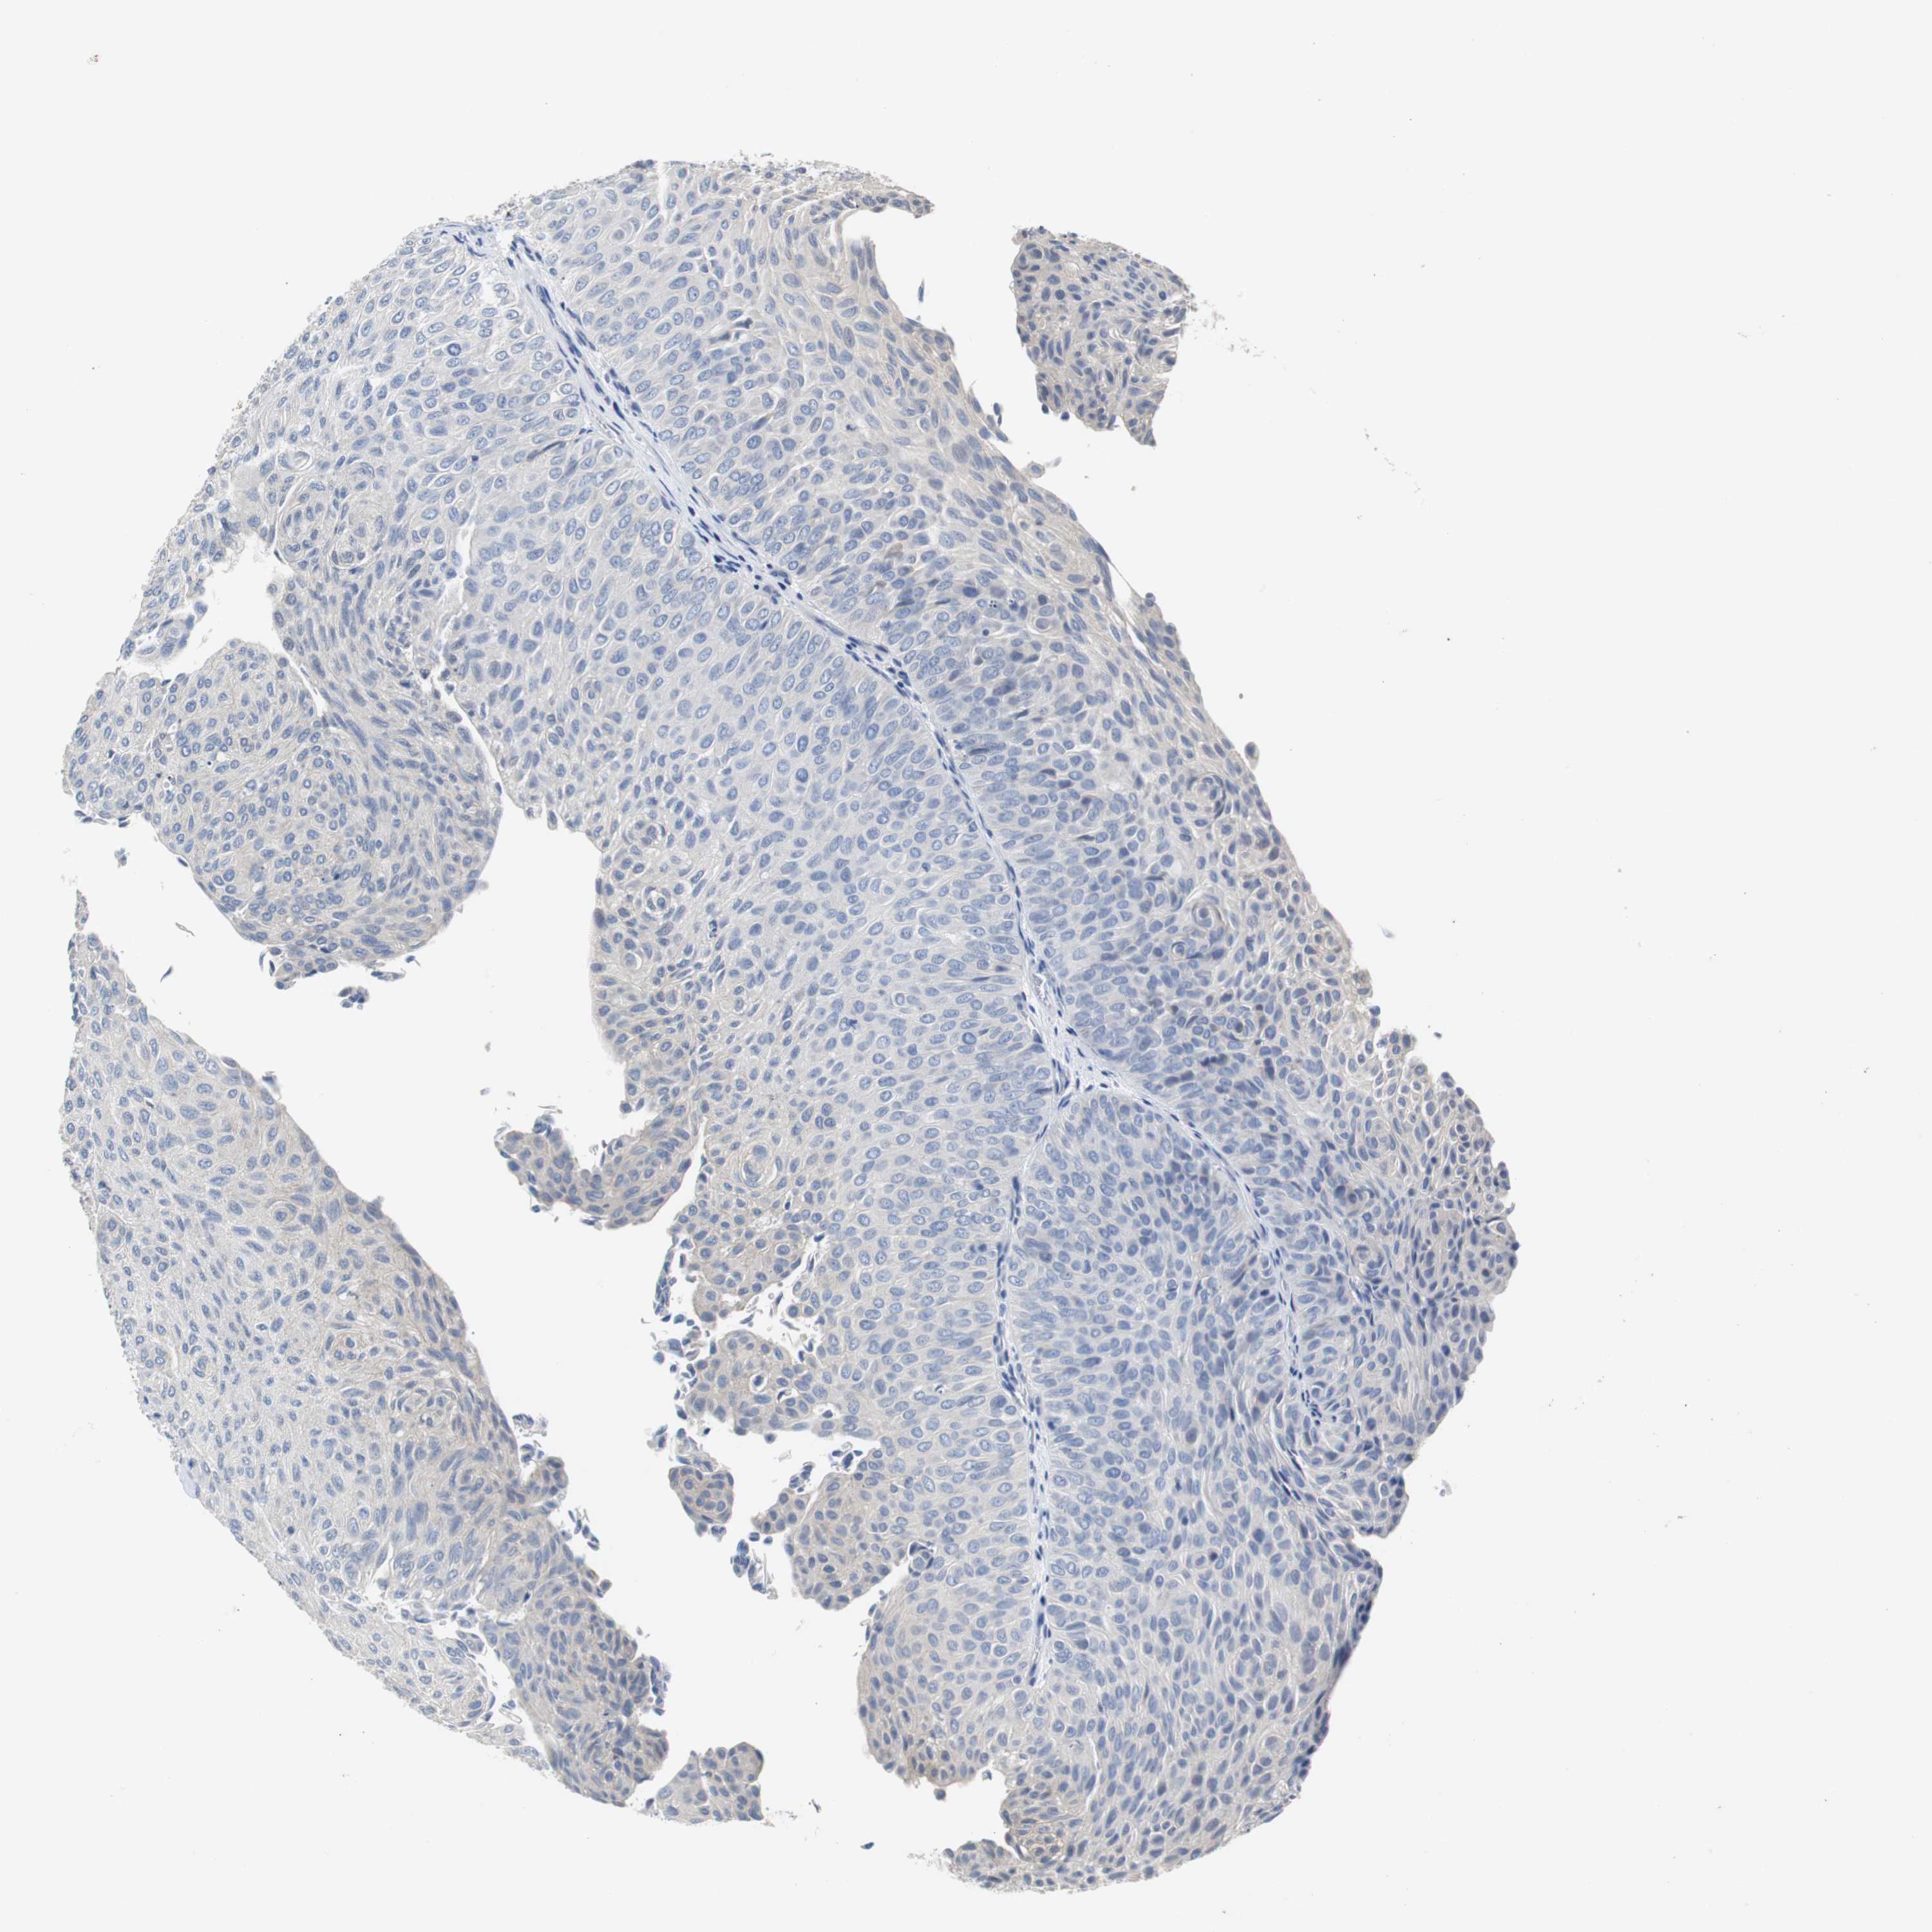

UROTHELIAL CANCER - Protein expressioni

A mouse-over function shows sample information and annotation data. Click on an image to view it in a full screen mode. Samples can be filtered based on level of antibody staining by selecting one or several of the following categories: high, medium, low and not detected. The assay and annotation is described here.

Note that samples used for immunohistochemistry by the Human Protein Atlas do not correspond to samples in the TCGA dataset.

Antibody stainingi

Antibody staining in the annotated cell types in the current human tissue is reported as not detected, low, medium, or high, based on conventional immunohistochemistry profiling in selected tissues. This score is based on the combination of the staining intensity and fraction of stained cells.

Each image is clickable and will lead to virtual microscopy that enables deeper exploration of all samples and also displays staining intensity scores, fraction scores and subcellular localization as well as patient and tissue information for each sample.

Antibody HPA006277

Antibody HPA006507

Antibody CAB017027

Staining

High

Medium

Low

Not detected

Intensity

Strong

Moderate

Weak

Negative

Quantity

>75%

75%-25%

<25%

None

Location

Nuclear

Cytoplasmic/membranous

Cytoplasmic/membranous,nuclear

Urothelial carcinoma, Low grade

Urothelial carcinoma, High grade